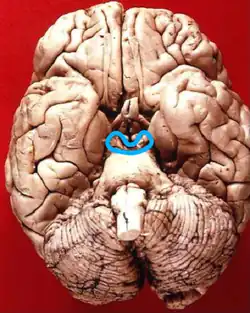

Inferior view in which the midbrain is encircled blue.